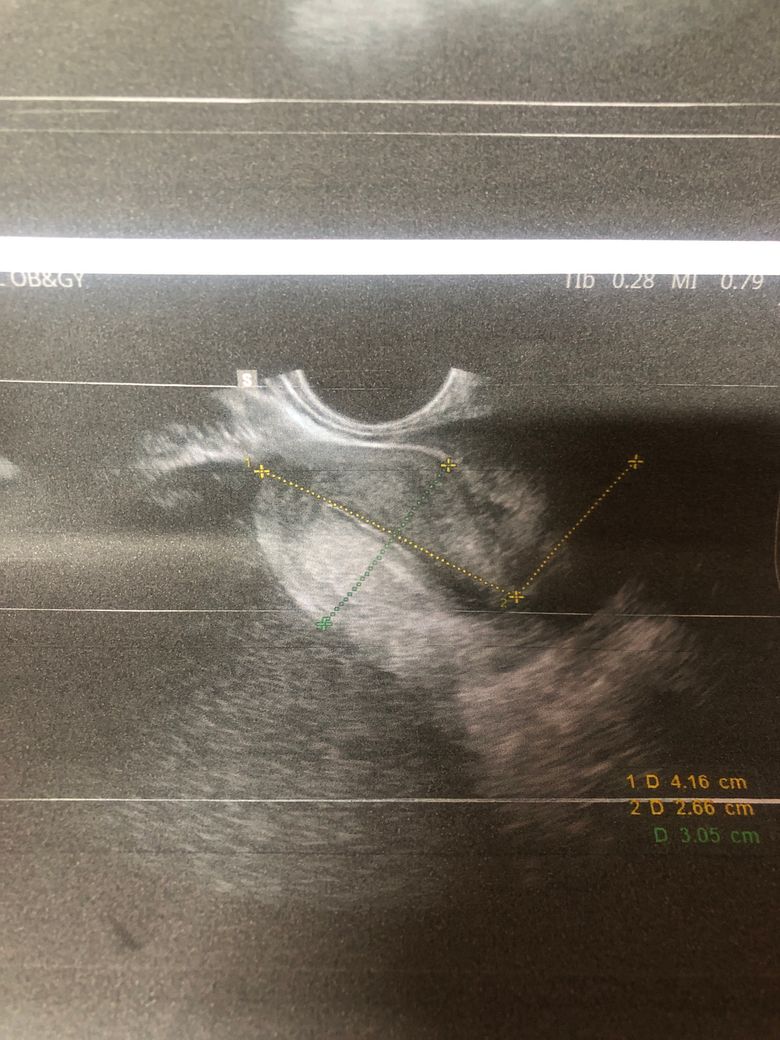

산부인과 검사 했는데요 혹이 있다고 해서 수술해야 한다고 하는데 꼭 수술밖에 답이 없나요?ㅠ(자궁쪽은 아닌거 같고 어디에 난 혹인지 정확히 모르겠다고 합니다)

• 3번 째 사진

• 골반 내부의 혹이 11cm나 된다면 크기가 매우 큰 것입니다. 현실적으로 수술적으로 제거하는 것이 가장 합리적이고 적절한 판단으로 보입니다만, 정확한 것은 큰 병원에서 추가적으로 정밀 검사를 하고 자세하게 파악한 뒤 새롭게 판단 받으시는 것이 좋겠습니다.